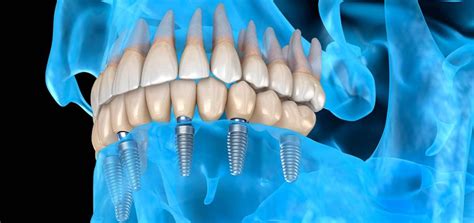

Los implantes dentales sin tornillos o también conocidos como implantes subperiósticos son un tipo de tratamiento que se utilizan en personas con poco hueso mandibular o maxilar. A diferencia de los implantes tradicionales, los subperiósticos no se insertan directamente en el tejido óseo, sino que se colocan bajo la encía y alrededor del hueso maxilar o mandibular con unas pequeñas inserciones laterales que permiten mayor fijación y estabilidad.

- Brindan máxima estabilidad y fijación: este tipo de implante se apoya sobre una estructura amplia y metálica que permite una fijación segura y estable.

- Mejora la estética y funcionalidad: gracias a esta técnica existe una base sólida para la prótesis dental, lo que permite que el paciente pueda sonreír y masticar mejor.

- Colocación de la prótesis: Toda rehabilitación con implantes sin tornillos consta de dos fases, en la primera se coloca una prótesis provisional, la cual viene prefabricada y permite al paciente tener dientes apenas termina la intervención. Una vez superada la etapa de integración se procede a la toma de medidas para la fabricación de una prótesis definitiva, puede ser de metal porcelana, metal acrílico o de zirconio.